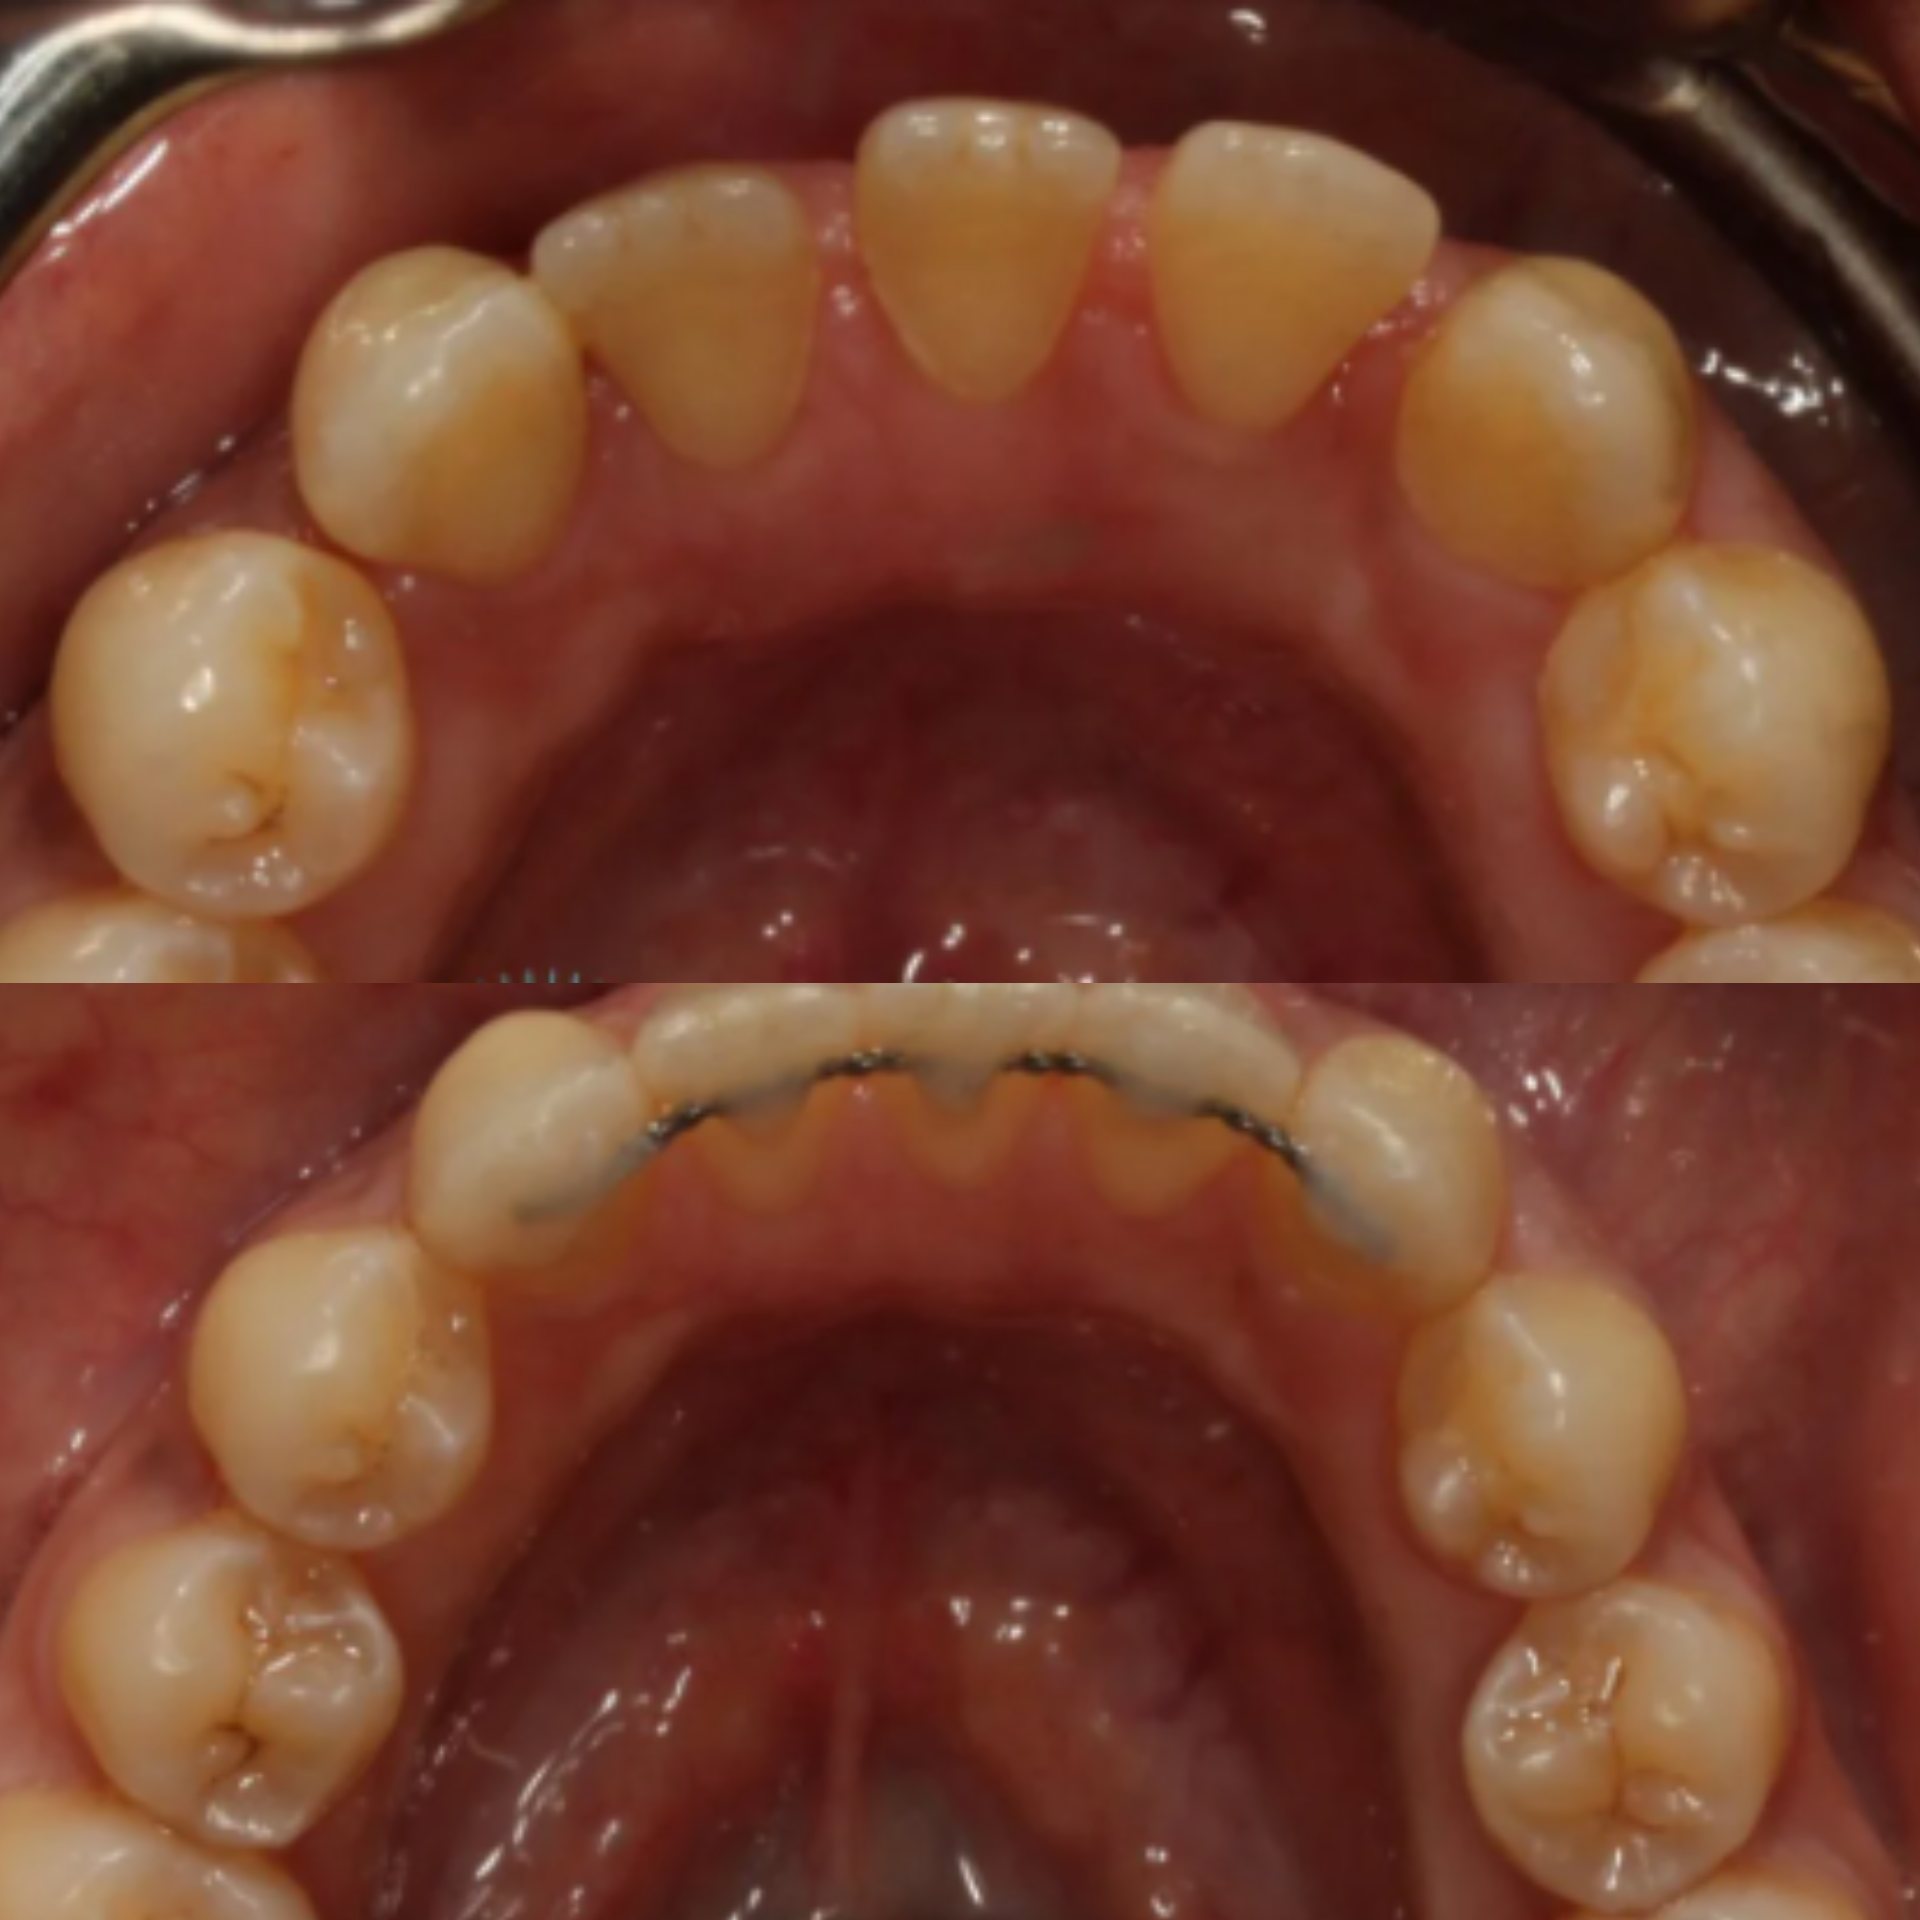

At Elite Dental Group, we provided emergency care that included root canal treatment on the upper central incisors. Dr. Satish Palayam performed an immediate implant placement for the right lateral incisor and completed a crown lengthening procedure on the palatal side of the right central incisor to support proper restoration. A provisional bridge was then placed to maintain both function and esthetics throughout the healing phase.

After a four month healing period, the final crowns were placed on the central incisors, and the implant for the right lateral incisor was successfully restored and finalized.